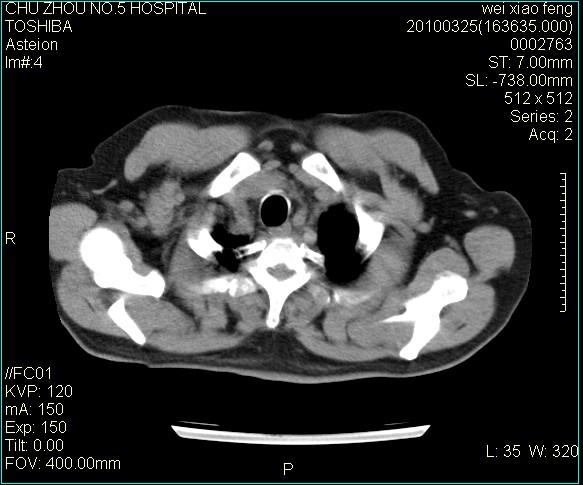

男,60岁,反复咳、痰、喘3月,加重3天。

双肺间质性改变。

间质性肺炎伴间质纤维化!不排除伴有职业病!

考虑尘肺